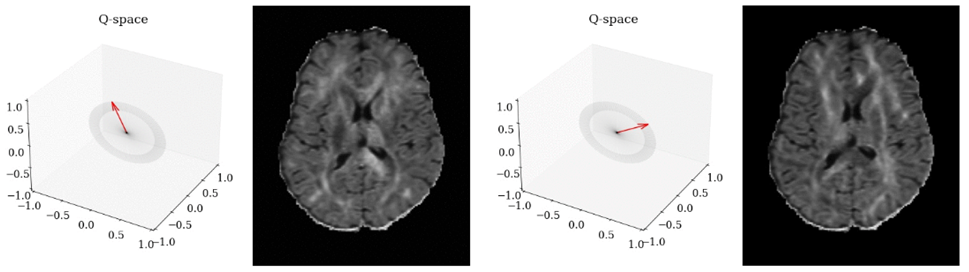

Кроме того, существуют ткани с неодинаковым по разным направлениям коэффициентом диффузии, что связано с наличием структур, вдоль которых диффузия происходит более свободно, чем в поперечном направлении. В связи с этим направление векторов градиентов часто имеет не меньшее значение, чем числовые характеристики, сведенные в b-фактор. Для учета этих особенностей там, где это важно, используется диффузионно-тензорная (Diffusion Tensor Imaging, DTI) или диффузионно-спектральная визуализация (Diffusion Basis Spectrum Imaging, DBSI).

для одного и того же b-фактора [источник]